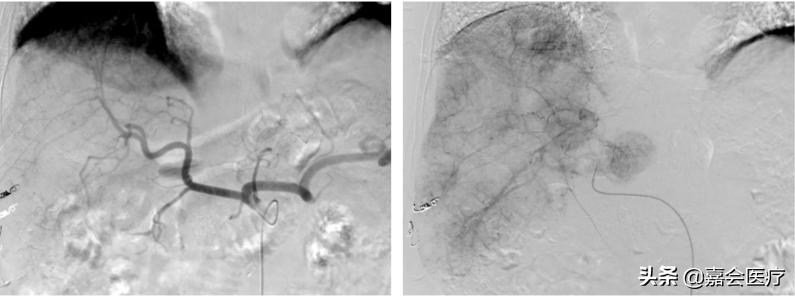

图:术中肝动脉显影